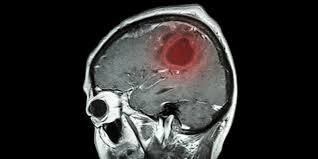

뇌종양은 뇌 조직안에

세균들이 침입하여

뇌속에서 염증을

만들고 고름을 만들어

뇌종양을 생기게 한다

뇌종양의 크기가 커지면 커질수록

뇌안에서 압박이 생기고 늦을수록

치사율은 다른 암보다 치명적이다

뇌종양의 초기 발견

뇌종양이라고 해서 전부

악성은 아닐수도 있다

정말 다행인것이 초기에 발견하게 되면

거의 완치가 가능하므로

절망하지 않아도 된다